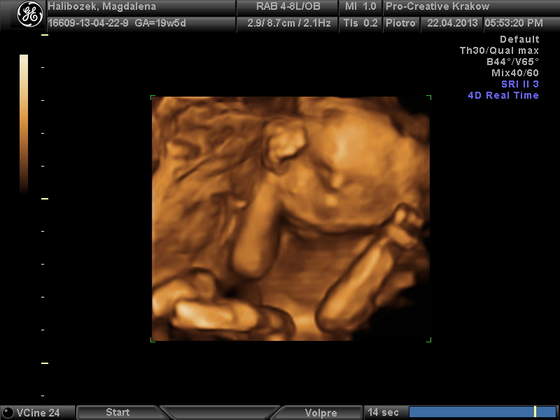

) Jest troszke młodsza wg usg o 5 dni ale sie smiejemy z mezem ,że kolosem to ona nie będzie jak się wda w mamusie (bo ja w kapeluszu 160 cm mam;-)) Na pierwszy rzut Zoska się rozkraczyła i pokazała piękną muszelkę

a oto ona